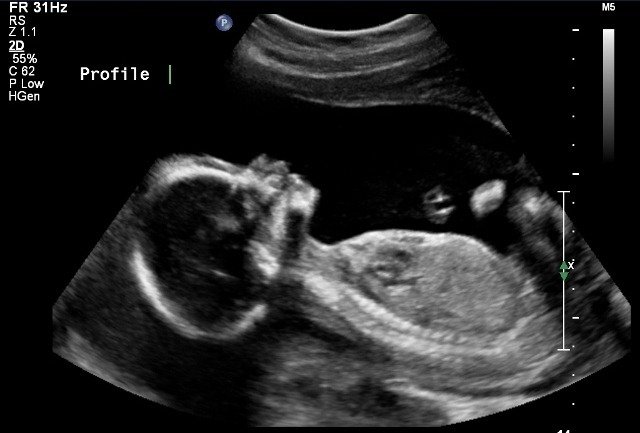

- Does not use radiation--preferred method for pregnant women

- Used to see babies in utero